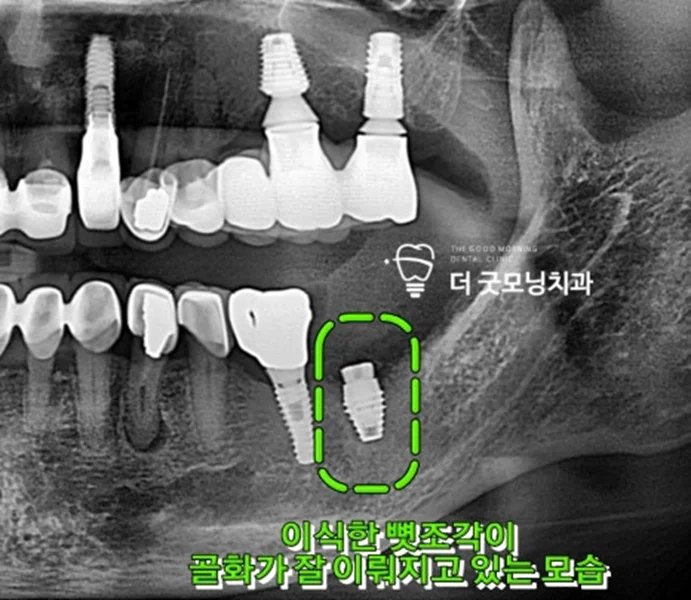

▲ 2개월 후 엑스레이 – 골화 및 픽스처 유착 확인

2개월 후 추적 관찰에서 이식한 골이식재가 잘 골화(骨化)되어 픽스처가 튼튼하게 유착된 것을 확인하였습니다. 고정력이 충분히 확보되어 저작력을 감당할 수 있는 상태가 되었습니다.